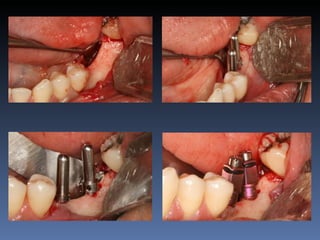

BOX 4

Ville Victorazzo Carmo

Idade – 20 anos

Sexo – Masculino

Raça – Caucasiana

ASA – I

Data- 27-04-2012

Diagnóstico: Desdentado da zona 2.1,

pré-regenerada.

Plano de tratamento: Instalação de implante endo-

ósseos ( 2.1 ) para reabilitação protética fixa.